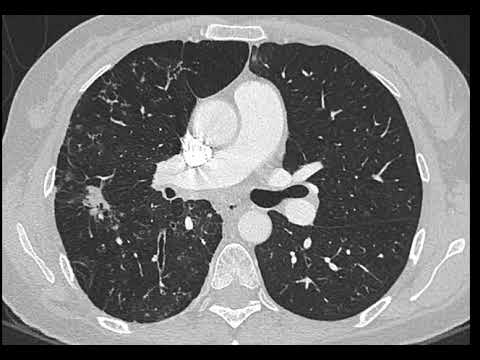

Bronchiectasis with lung nodule